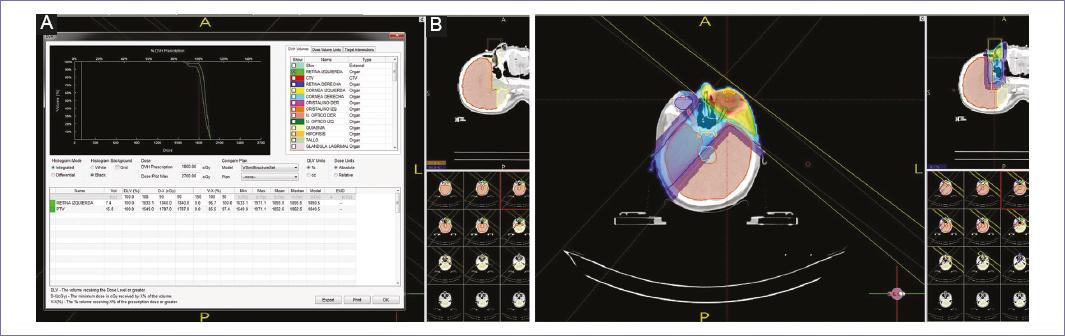

Nosotros reportamos el caso de una paciente de 38 años, mesomórfica, sin comorbilidades, nulípara y con antecedente de opsomenorrea, quien presentó 2 años antes sangrado transvaginal continuo asociado a dolor pélvico crónico y pérdida de peso de 8 kilogramos en 3 meses. Fue diagnosticada con carcinoma de endometrio pobremente diferenciado invasor con diferenciación adenoescamosa extensa y necrosis tumoral del 40%, etapa IVB de la FIGO, con actividad tumoral metastásica en parénquima pulmonar, ganglionar aortocava, cadenas ilíacas internas y ósea con destrucción lítica de sínfisis del pubis del lado izquierdo con componente de tejidos blandos heterogéneo, infiltración a los músculos obturador externo e interno ipsilateral; con antígeno carbohidratado 125 inicial de 37.07 UI/ml y carcinoembrionario de 1.15 ng/ml. Se realizó tratamiento con radioterapia paliativa a dosis de 30 Gy en 10 fracciones a pelvis ósea y primario, y posteriormente 6 ciclos de quimioterapia paliativa con cisplatino y adriamicina; con progresión pulmonar de la enfermedad, se administró 1 ciclo más de adriamicina, con nueva progresión a sistema nervioso central, por lo que se inició radioterapia paliativa a holocráneo con dosis de 30 Gy en 10 fracciones. La paciente refería visión borrosa, dolor ocular izquierdo, inadecuada ubicación espacial de los objetos, con TC (Fig. 1) en la que se apreciaba engrosamiento nodular focal a nivel de retina, de 0.4 cm en eje anteroposterior, por lo que fue referida a Oftalmología, quienes reportan en su valoración:agudeza visual (AV) ojo derecho (OD) 20/40 y ojo izquierdo (OI) 20/50, con distorsión temporal de la imagen; en fondo de ojo izquierdo se observa masa sobreelevada de color blanquecino subretiniana en cuadrantes temporales de más de 10 dd; se realizó ecografía modo B de ese ojo (Fig. 2) en la que se observa la imagen anexa, masa sólida dependiente de coroides y desprendimiento de retina sobre el área de la lesión, concluyendo enfermedad metastásica coroidea en ojo izquierdo. Con los datos anteriores, se le brindó tratamiento con radioterapia paliativa a metástasis coroidea, una semana posterior a finalizar teleterapia a holocráneo, con dosis de 18 Gy en 10 fracciones, con acelerador lineal, técnica conformal 3D, energía de 6 MV, con fotones, dos campos laterales (Fig. 3), finalizando tratamiento con adecuada tolerancia, movimientos oculares de ojo izquierdo conservados. Dos días posteriores a finalizar la teleterapia a ojo izquierdo, se realizó nueva TC de tórax, abdomen y pelvis, en donde se evidenció nueva progresión de la enfermedad pulmonar, a mediastinales, axilar y a glándulas suprarrenales. La paciente falleció 11 días después de la finalización de radioterapia paliativa a ojo izquierdo, por lo que no fue posible valorar objetivamente la respuesta al tratamiento en cuanto a metástasis de coroideas.

En el caso que se describe, la paciente recibió en primera instancia radioterapia a holocráneo, paliativa, con dosis de 30 Gy en 10 fracciones, posteriormente teleterapia paliativa a ojo izquierdo, se ajustó dosis de radioterapia por tratamiento reciente a holocráneo, con dosis de 18 Gy en 10 fracciones, la dosis que se aplicó a PTV-volumen blanco de planeación (ojo izquierdo) al 50%, sumando la contribución de holocráneo, fue de 25.08 Gy DBE (dosis biológica equivalente) y el 90% recibió 20 Gy DBE; sin embargo no se logró valorar la respuesta, ya que la paciente falleció tras finalizar el tratamiento.